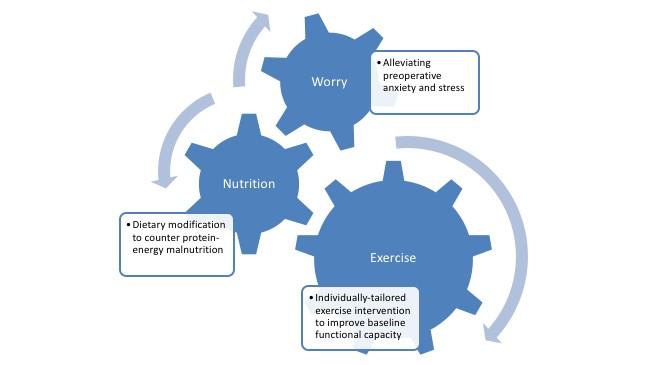

Can older, frail patients benefit from ‘prehabilitation’ before heart surgery?

Credit: Canadian Journal of Cardiology Philadelphia, June 27, 2018 - High risk, frail heart patients might derive benefits from "prehabilitation,"...